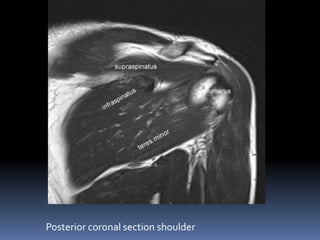

Posterior coronal section shoulder

Posterior sections of shoulder